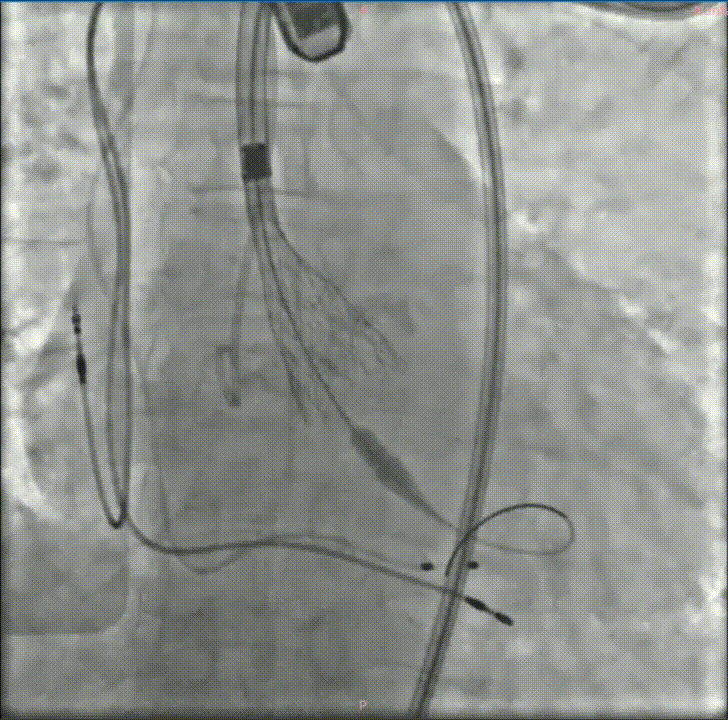

经过充分的术前评估和准备,修建成教授带领由医院心内、超声、麻醉、放射等多学科成员组成的手术团队,开始了这台TAVR手术。

穿刺、置管、跨瓣、扩张、释放瓣膜、测压、检测、拔管、手术结束……当天的DSA手术台上,修建成教授和团队有条不紊地完成着每一个步骤。术中的每一个步骤、每一个节点、每一个动作,团队每位成员都十分娴熟。最终成功在预定位置精准植入瓣膜。

深度评估

释放后造影

后扩

瓣膜植入后立即进入工作状态,术后造影显示瓣膜工作状态良好,无瓣周漏及明显跨瓣压差;冠脉无阻挡,无传导阻滞

采访中,修建成教授欣慰地分享了手术效果:“手术之后的结果也验证了我们术前的分析和想法。从影像学结果分析来看,我们把瓣周漏减少到非常低的水平,同时瓣膜的扩张、展开都非常好,可以说达到一个非常理想的结果。”